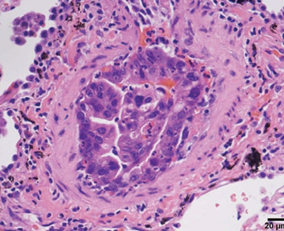

a) Presence of numerous macrophages containing hemosiderin, cholesterol clefts, mixed with inflammatory cells and cellular debris. b) Presence of fibrocollagenous capsule and intraluminal necrosis (Courtesy Dr. V. Penopoulos)